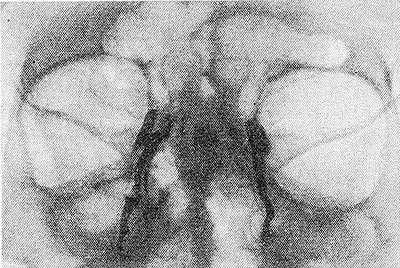

Рис. 1. Схема дакриоцистограммы здорового человека (в лобно-носовой проекции): 1 —лобные пазухи; 2 — орбиты; 3 — клетки решетчатого лабиринта; 4 — слезные канальцы; 5 — слезные мешки; 6 — слезно-носовые каналы; 7 — гайморовы пазухи; 8 — носовые ходы (слезные мешки и слезно-носовые каналы заполнены контрастным веществом).

Рис. 2. Дакриоцистограмма. На рисунке слева картина хронического дакриоцистита: слезный мешок и канал расширены, частично закупорено носовое отверстие. Справа без изменений (слезные мешки и слезно-носовые каналы заполнены контрастным веществом).

На дакриоцистограммах рассматривают изображение орбит, лобных, решетчатых, верхнечелюстных пазух и их пневматизацию, состояние полости носа и его костных стенок. Затем исследуют все части слезоотводящих путей — слезные канальцы, слезные мешки и слезно-носовые каналы (рис. 1 и 2), определяют их расположение, величину, форму, очертания, локализацию стриктур, расположение и ход свищей и функциональное состояние (момент появления контрастного вещества в полости носа, время опорожнения путей, неровность очертаний, обусловленную воспалительным набуханием слизистой оболочки или ростом грануляций, наличие расширения и дивертикулярных выпячиваний).